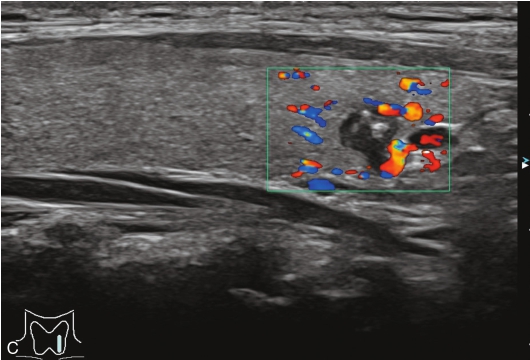

男性,52岁,外院发现甲状腺结节,为求进一步诊治收入我院。

甲状腺左叶中下部见一混合回声结节,边界清,形态规则,中心部可见斑状强回声,CDFI显示周边可见环状血流信号,其内可见丰富血流信号,见图1-3-18。

该结节早于周围腺体组织增强,结节内部呈高增强表现,可见部分无增强区;结节晚于周围腺体组织消退,仍呈高增强表现;结节周边可见均匀高增强环,甲状腺被膜未见明显中断,见图1-3-19、ER1-3-9。

(1)结节增强早期早于腺体增强或与腺体同步增强,增强晚期晚于腺体消退或与腺体同步消退。

(2)结节内部呈均匀或不均匀弥漫性等增强或高增强,增强水平通常高于周围腺体。

(3)结节与周围腺体分界清晰,形态较规则。

(4)部分结节周边可见均匀高增强环。

(5)结节周边被膜连续完整。

甲状腺滤泡性腺瘤通常为富血供病灶,其增强水平等于或高于周围腺体,并呈现“早增强,晚消退”的特点,重点需要与滤泡性腺癌鉴别,腺瘤多边界清晰、形态较规则,造影时结节周围的高增强环厚薄一致、较为均匀,结节周边被膜连续完整、无浸润表现,颈部淋巴结无异常肿大等。而滤泡性腺癌边界不清、呈浸润性生长表现,周边高增强环消失或厚薄不均,如发现颈部异常肿大淋巴结及被膜连续性中断等,需要高度警惕甲状腺恶性肿瘤。

图1-3-18 甲状腺滤泡性腺瘤常规超声声像图

A.甲状腺左叶纵切面超声图像;B.结节内部点状及斑状强回声;C.CDFI血流图

图1-3-19 甲状腺滤泡性腺瘤超声造影图

A.注入造影剂后9s;B.注入造影剂后11s;C.注入造影剂后16s;D.注入造影剂后27s